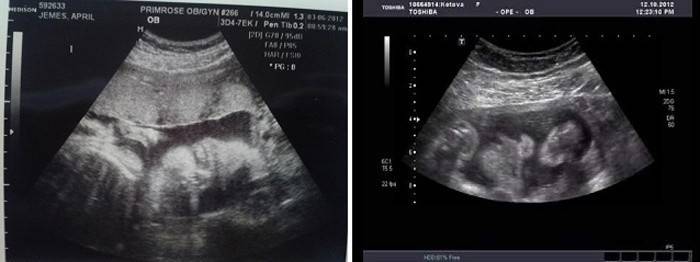

Ultrazvukové vyšetrenie (Uzi)

V priebehu 30 až 32 týždňov sa často uskutočňuje tretie plánované ultrazvukové vyšetrenie plodu, aby sa zistili neskoré malformácie a vrodené chyby. Ultrazvuk okrem toho monitoruje stav plodu, placentu a maternicu. V tomto období je možné vykonávať konvenčné aj 3D-ultrazvuk, ale od tridsiatich týždňov sa dieťa pozerať kvôli jeho veľkosti je úplne ťažké, zvyčajne sú viditeľné iba časti tela.

Hlavné ukazovatele ultrazvuku stanovené lekárom sú hrúbka a stupeň zrelosti placenty, stav uteroplacentálneho prietoku krvi, množstvo plodovej vody a ich stav, poloha placenty, vzdialenosť od jej okraja k vnútornému hltanu krčka maternice. Lekár tiež starostlivo skúma všetky časti tela plodu a jeho vnútorné orgány, najmä obličky, srdce, mozog. Súbežne s ultrazvukom sa zvyčajne vykonáva dopplerometria - hodnotenie stavu prietoku krvi v srdci a krvných ciev plodu, steny maternice a placenty, pupočnej šnúry.